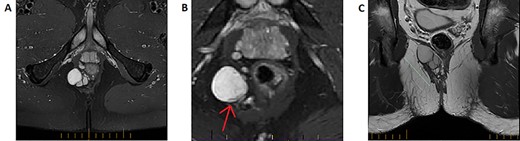

A magnetic resonance imaging (MRI) was performed demonstrating a multiseptated perianal cystic collection on the right side ~3 cm from the anal verge extending craniocaudally (Fig. 2A–C). The working diagnosis at the time was a complex congenital cyst. A thin rim of T2-hypointense material was present on its medial wall indicating a solid component, which raises the possibility of malignant potential (Fig. 2B) [3]. A fluorodeoxyglucose (FDG)-positron emission tomography (PET) scan was performed accordingly and while the majority of the cyst was poorly FDG avid, the solid component was difficult to assess due to surrounding artefact from the adjacent rectum (Fig. 1B). The decision was made to proceed with surgical excision.

T2-weighted MRI imaging. A: Axial slice taken below the perineal floor demonstrating a multilobulated T2-hyperintense lesion suggestive of a predominantly cystic structure. B: A zoomed slice on the same sequence taken cephalad to (A) indicates that the structure is inhomogeneous—a rim of T2-hypointensity exists at its medial end (red arrow). This represents a solid component and would raise suspicion for malignant potential. C: Coronal slice of the T2 fat-suppression sequence MRI highlighting the cranio-caudal extension of the lobulated structure.